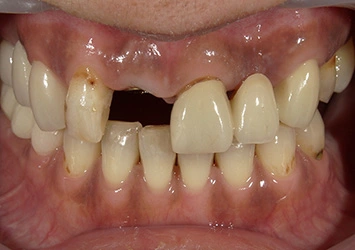

治療前

治療前写真 恵比寿南DENTAL

治療後

治療後写真 恵比寿南DENTAL

施術内容

【20代女性】

右下7番の歯根破折してしまい保存不可能となってしまった歯を抜歯し、インプラント埋入

治療期間

5ヶ月

リスク

術中の不可抗力によるトラブル(出血など)、術後注意事項を守らないことによる疼痛、感染、上部構造装着後口腔内清掃を怠ったことによるインプラント周囲組織の炎症

副作用

治療後の口腔内清掃、及びメインテナンスを怠ったことによるインプラント周囲粘膜炎またはインプラント周囲炎

費用

インプラント埋入:30万円

ジルコニアクラウン:12万円